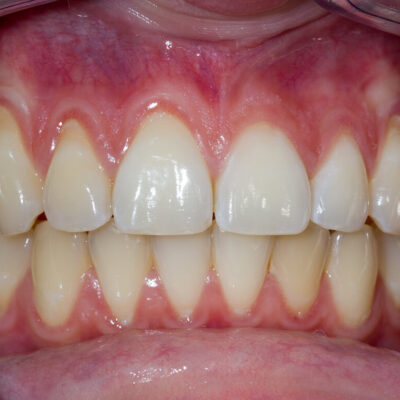

Visione schematica della Parodontite: gengive arrossate e ritirate, radice dentarie esposte e con calcoli di tartaro

Parodontite (piorrea)

La parodontite, più conosciuta con il nome di piorrea, è una malattia che nello stadio iniziale coinvolge i tessuti intorno alla radice del dente e dell’osso fino a provocare una mobilità del dente stesso, la formazione di tasche e la perdita dell’elemento dentale.

Sintomi

Anche se, come detto in precedenza, la malattia parodontale solitamente non provoca dolore, i segnenti sintomi dovrebbero essere considerati un campanello d’allarme: sanguinamento delle gengive, mobilità dentale, dolore durante lo spazzolamento, alito cattivo.